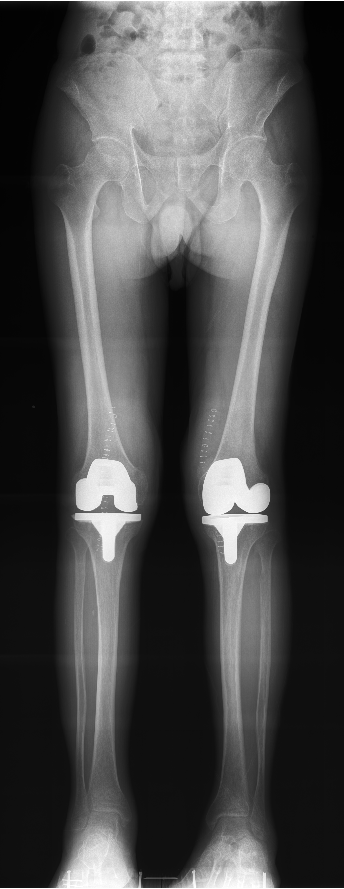

全自动全景成像(选配)

三次点击,两个步骤,一气呵成

全过程一分钟内完成,摄影条件智能设定,根据不同体厚智能曝光补偿,宽幅窄缝按需选择,无需往返机房调整机架位置,一气呵成自动全景成像